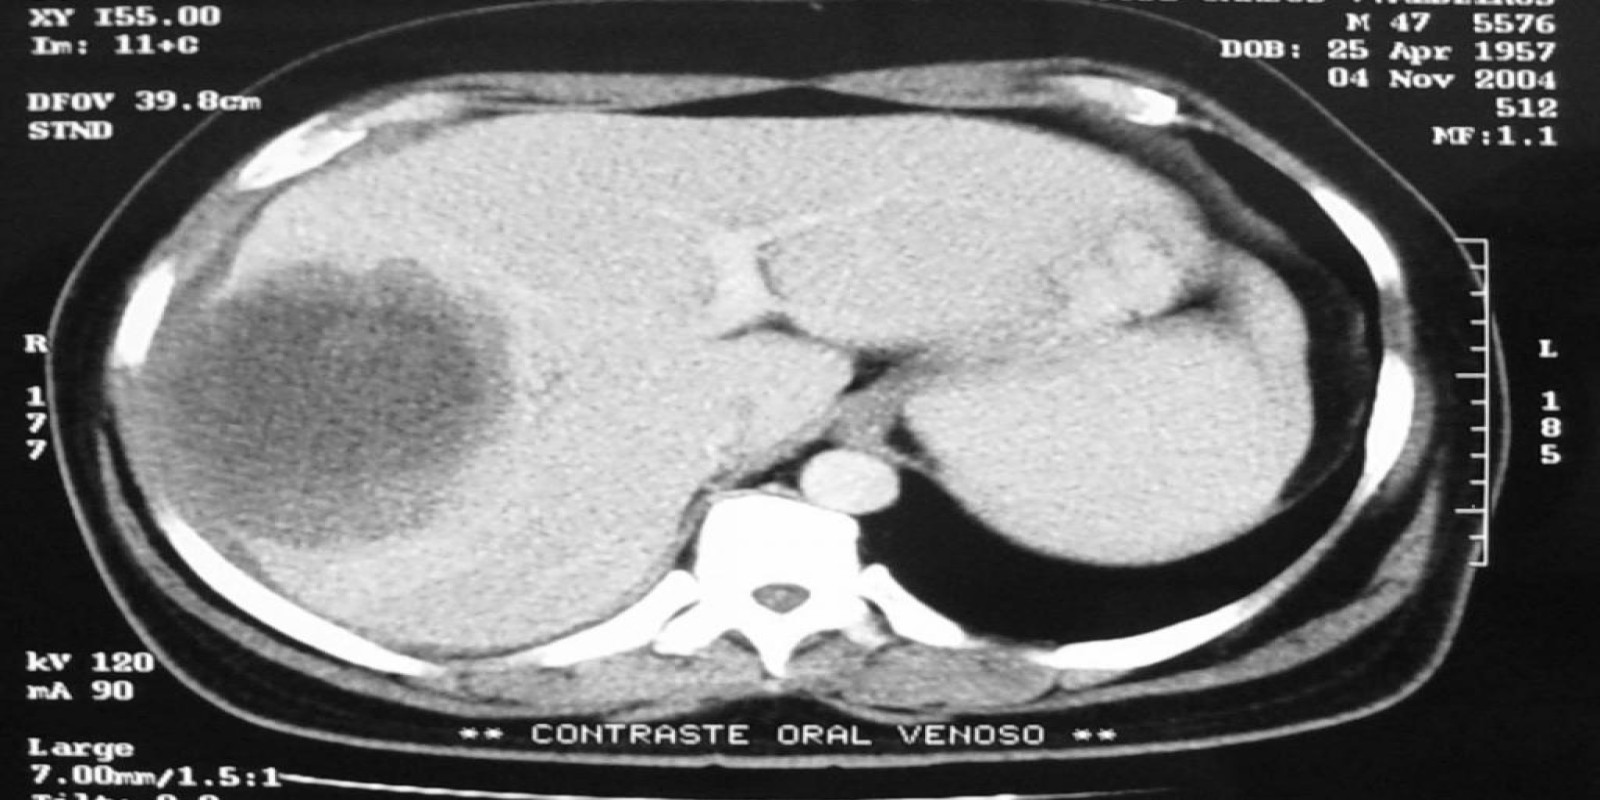

Abscesso Hepático

Liver abscess

Caso Código 042A de Abscesso Hepático

Cod.: 042A